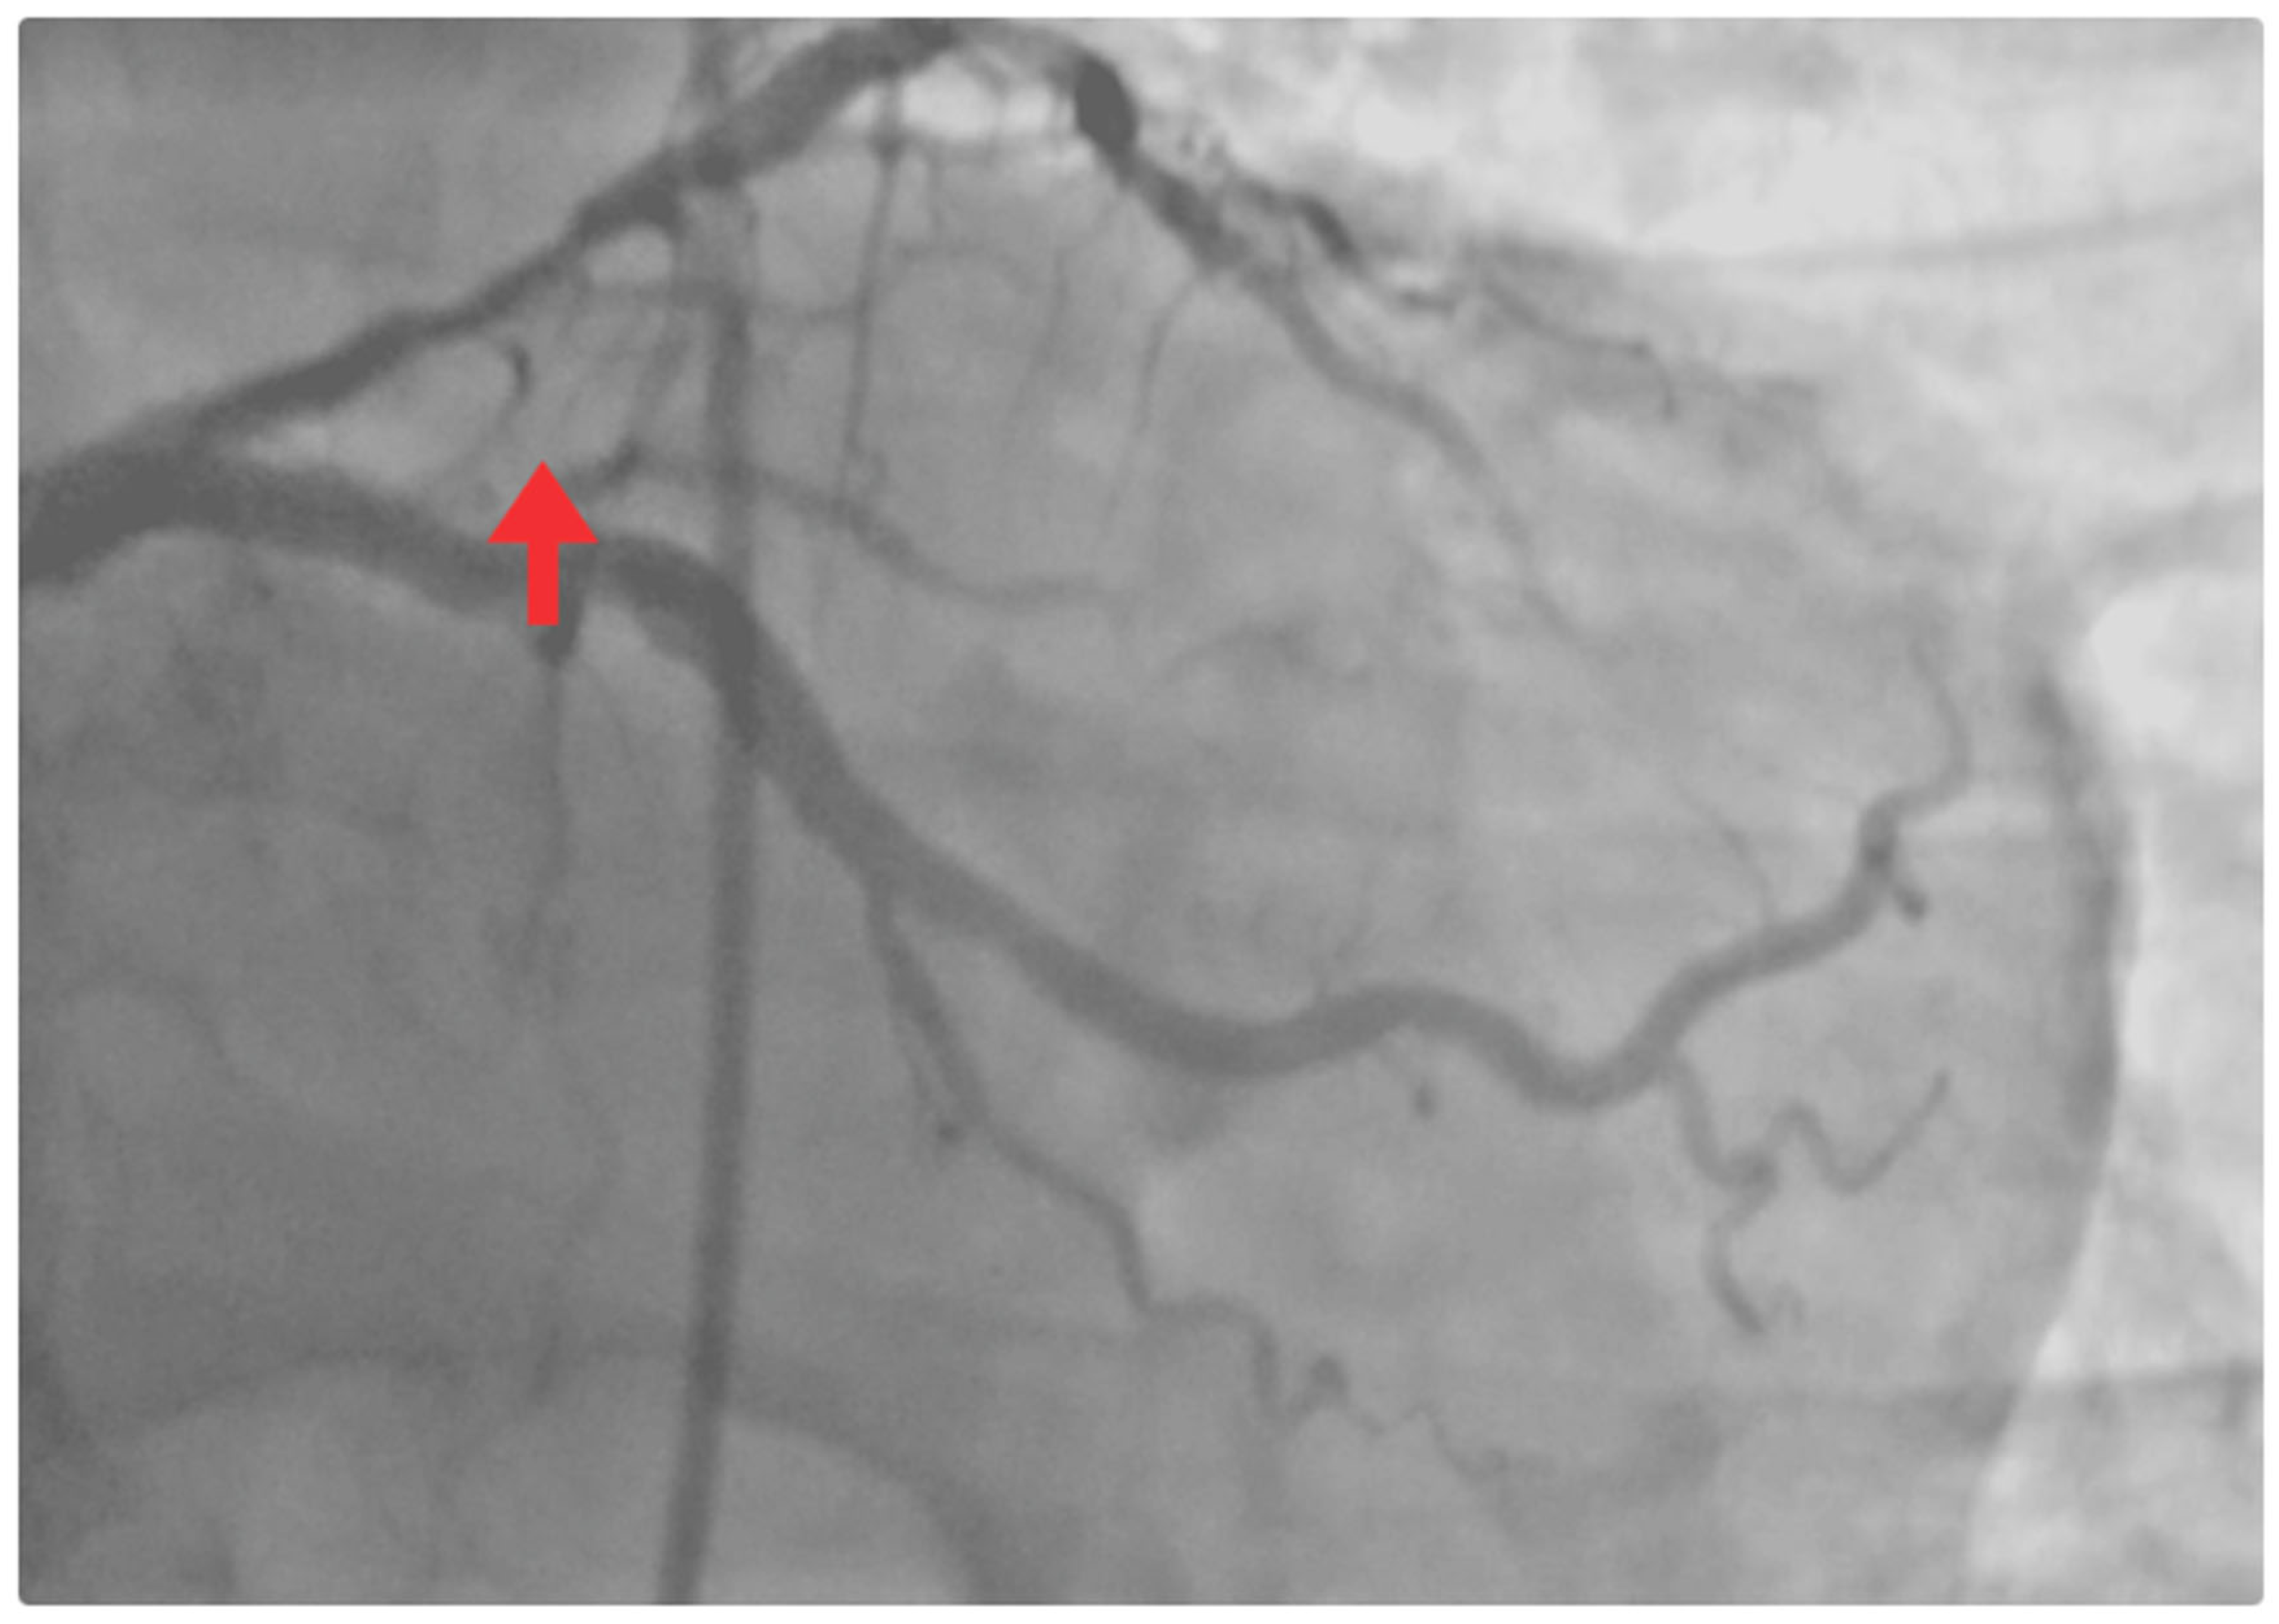

| 8 May | Mild retrosternal chest pain, absence of dyspnea, and improved ventilatory mechanics. | - | - | Coronary angiography: critical proximal LAD stenosis (>90%). Chronic atherosclerotic disease in the circumflex artery, without significant obstructive lesions. Percutaneous coronary intervention (PCI): angioplasty + drug-eluting stenting in the proximal LAD (TIMI 3 flow). |